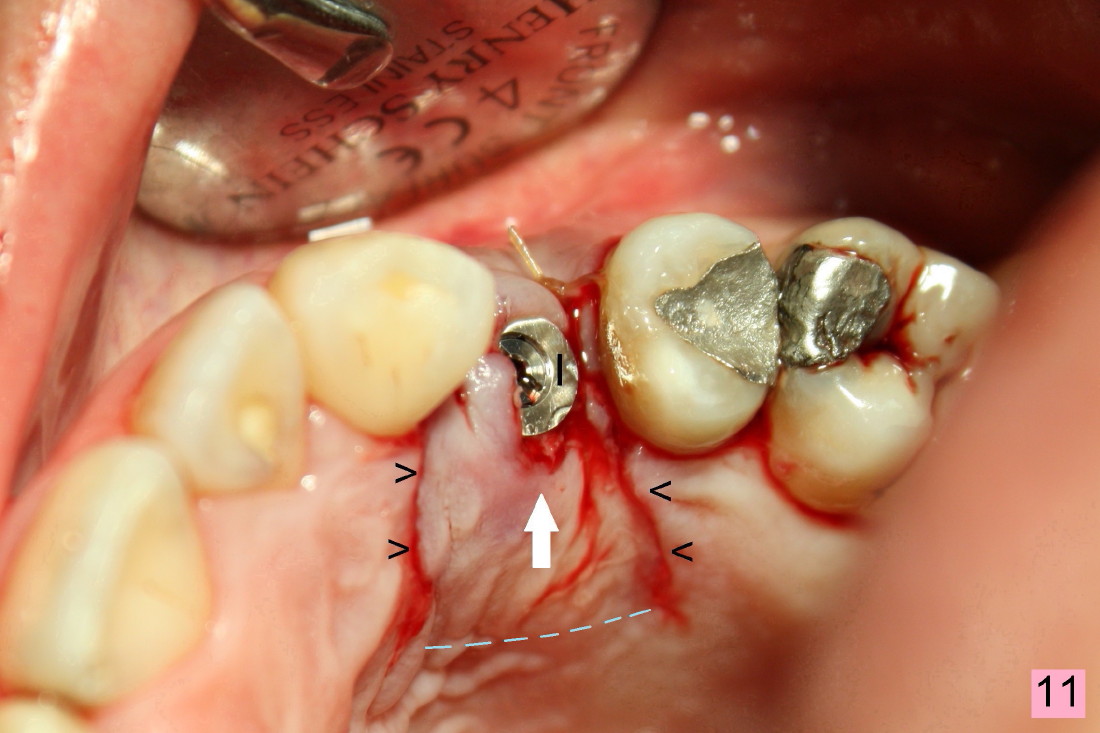

The closure of the socket involves raising and advancing both buccal and lingual flaps (Fig.10,11). When a crown is cemented, the patient is not pleased with recessive papillae (Fig.12 (arrowheads),13). It appears that flaps should be avoided to prevent cosmetic issue. Immediate implant is not enough for cosmetics; immediate provisional can close the extraction socket and support the papillae.